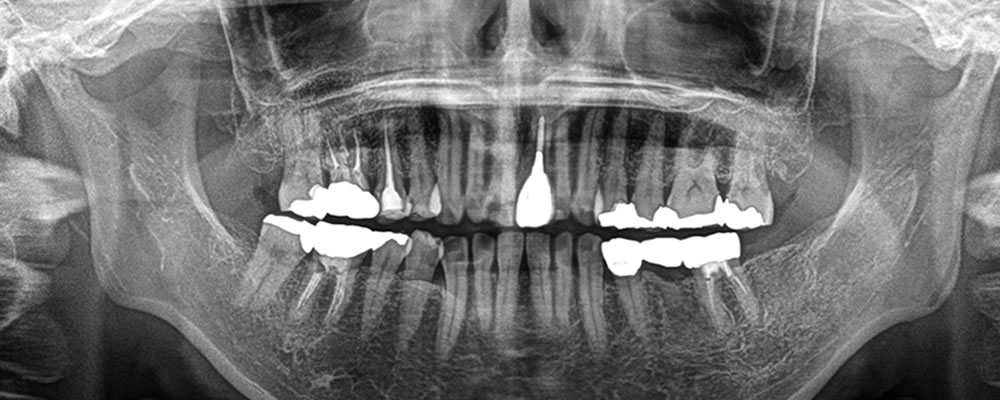

他院で抜歯した部分をインプラントで治療した症例

こちらの患者さまは、他院で抜歯した部位に歯を入れたいとのことで来院されました。

他院で抜歯後、特に問題なく噛むことはできていましたが、他の歯の負担をなるべく減らしたいとのことで、インプラントをご希望されました。